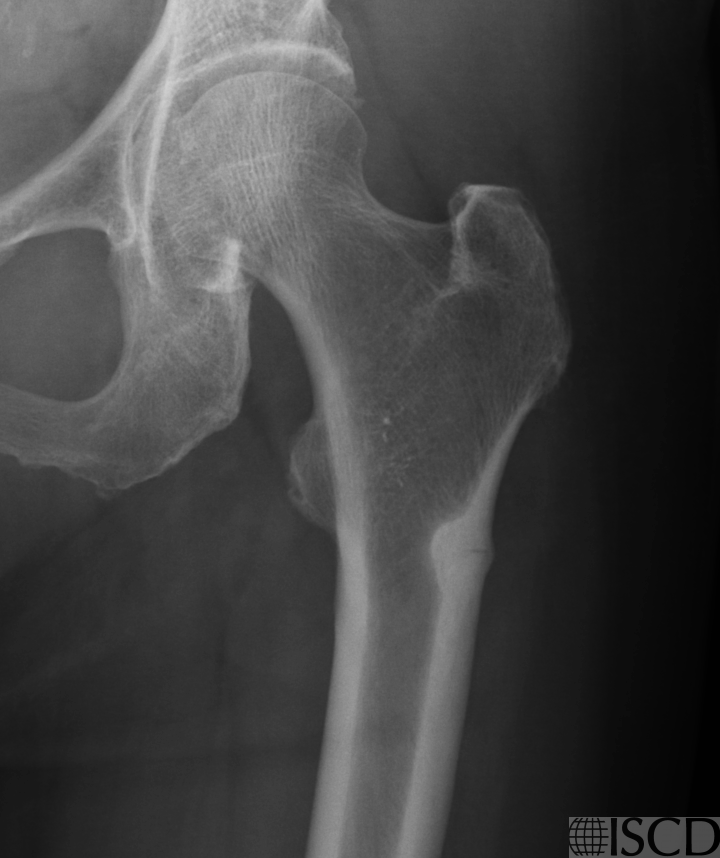

Figure 2A: Left hip x-ray

84 year old Asian female with 10 years of oral bisphosphonate therapy due to low bone mass (osteopenia) and breast cancer (aromatase inhibitor therapy). Left hip DXA image shows localized endosteal reaction lateral subtrochanteric femur, more prominent on the left side. Subsequent x-rays confirmed an incomplete left atypical femur fracture (AFF) with “dreaded black line” (no x-ray of the right hip available).